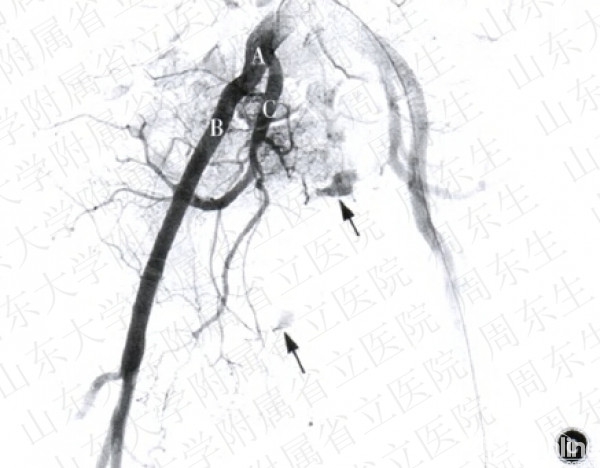

图2造影栓塞术止血手术及示意图a骨盆正位x线片示Tile分型A型骨盆骨折b动脉造影示意图示左侧髂内动脉的一个分支出现“冒烟”征,证明有动脉的活动性出血e行髂内动脉造影术示髂内动脉分支出血,典型的“冒烟”症,A为髂总动脉,B髂外动脉,c髂内动脉,箭头示出血点d示意图示注入明胶海绵.等栓塞材料行髂内动脉栓塞,栓塞后再次造影检查示动脉出血征象消失e行墨多髂内动脉栓塞术,再次造影示出血停止,箭头示髂内动脉栓塞部位

2.栓塞组:局麻后,患者取仰卧位,采用Seldinger法行股动脉穿刺插管(用带芯穿刺针穿透血管,拔出针芯,缓慢向外退针,至血液从针尾喷出,迅速插入导针后,拔出穿刺针,通过导丝引入导管至股动脉)。将5~7F猪尾导管置于腹主动脉分叉上2—3cm,注入对比剂造影,而后更换Cobra导管选择性地行髂内动脉造影,此时可发现动脉出血部位造影剂外渗,形成“冒烟”征(图2a~2c)。选择髂内动脉主干或分支动脉注入明胶海绵颗粒进行栓塞,再次造影复查,如出血征象消失则停止注入栓塞剂(图2d,2e)。栓塞组12例行髂内动脉主干栓塞,1例行骶正中动脉栓塞,4例行髂内动脉分支血管栓塞(闭孔动脉1例,臀上动脉3例)。